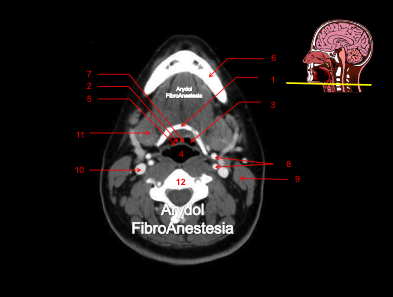

CORTE A NIVEL DE LA NASOFARINGE (CAVUM)

1.nasofaringe (cavum); 2. senos maxilares; 3. tabique nasal; 4. corenetes; 5.vía aérea fosas nasales; 6. trompa de Eustaquio; 7. rama mandibular